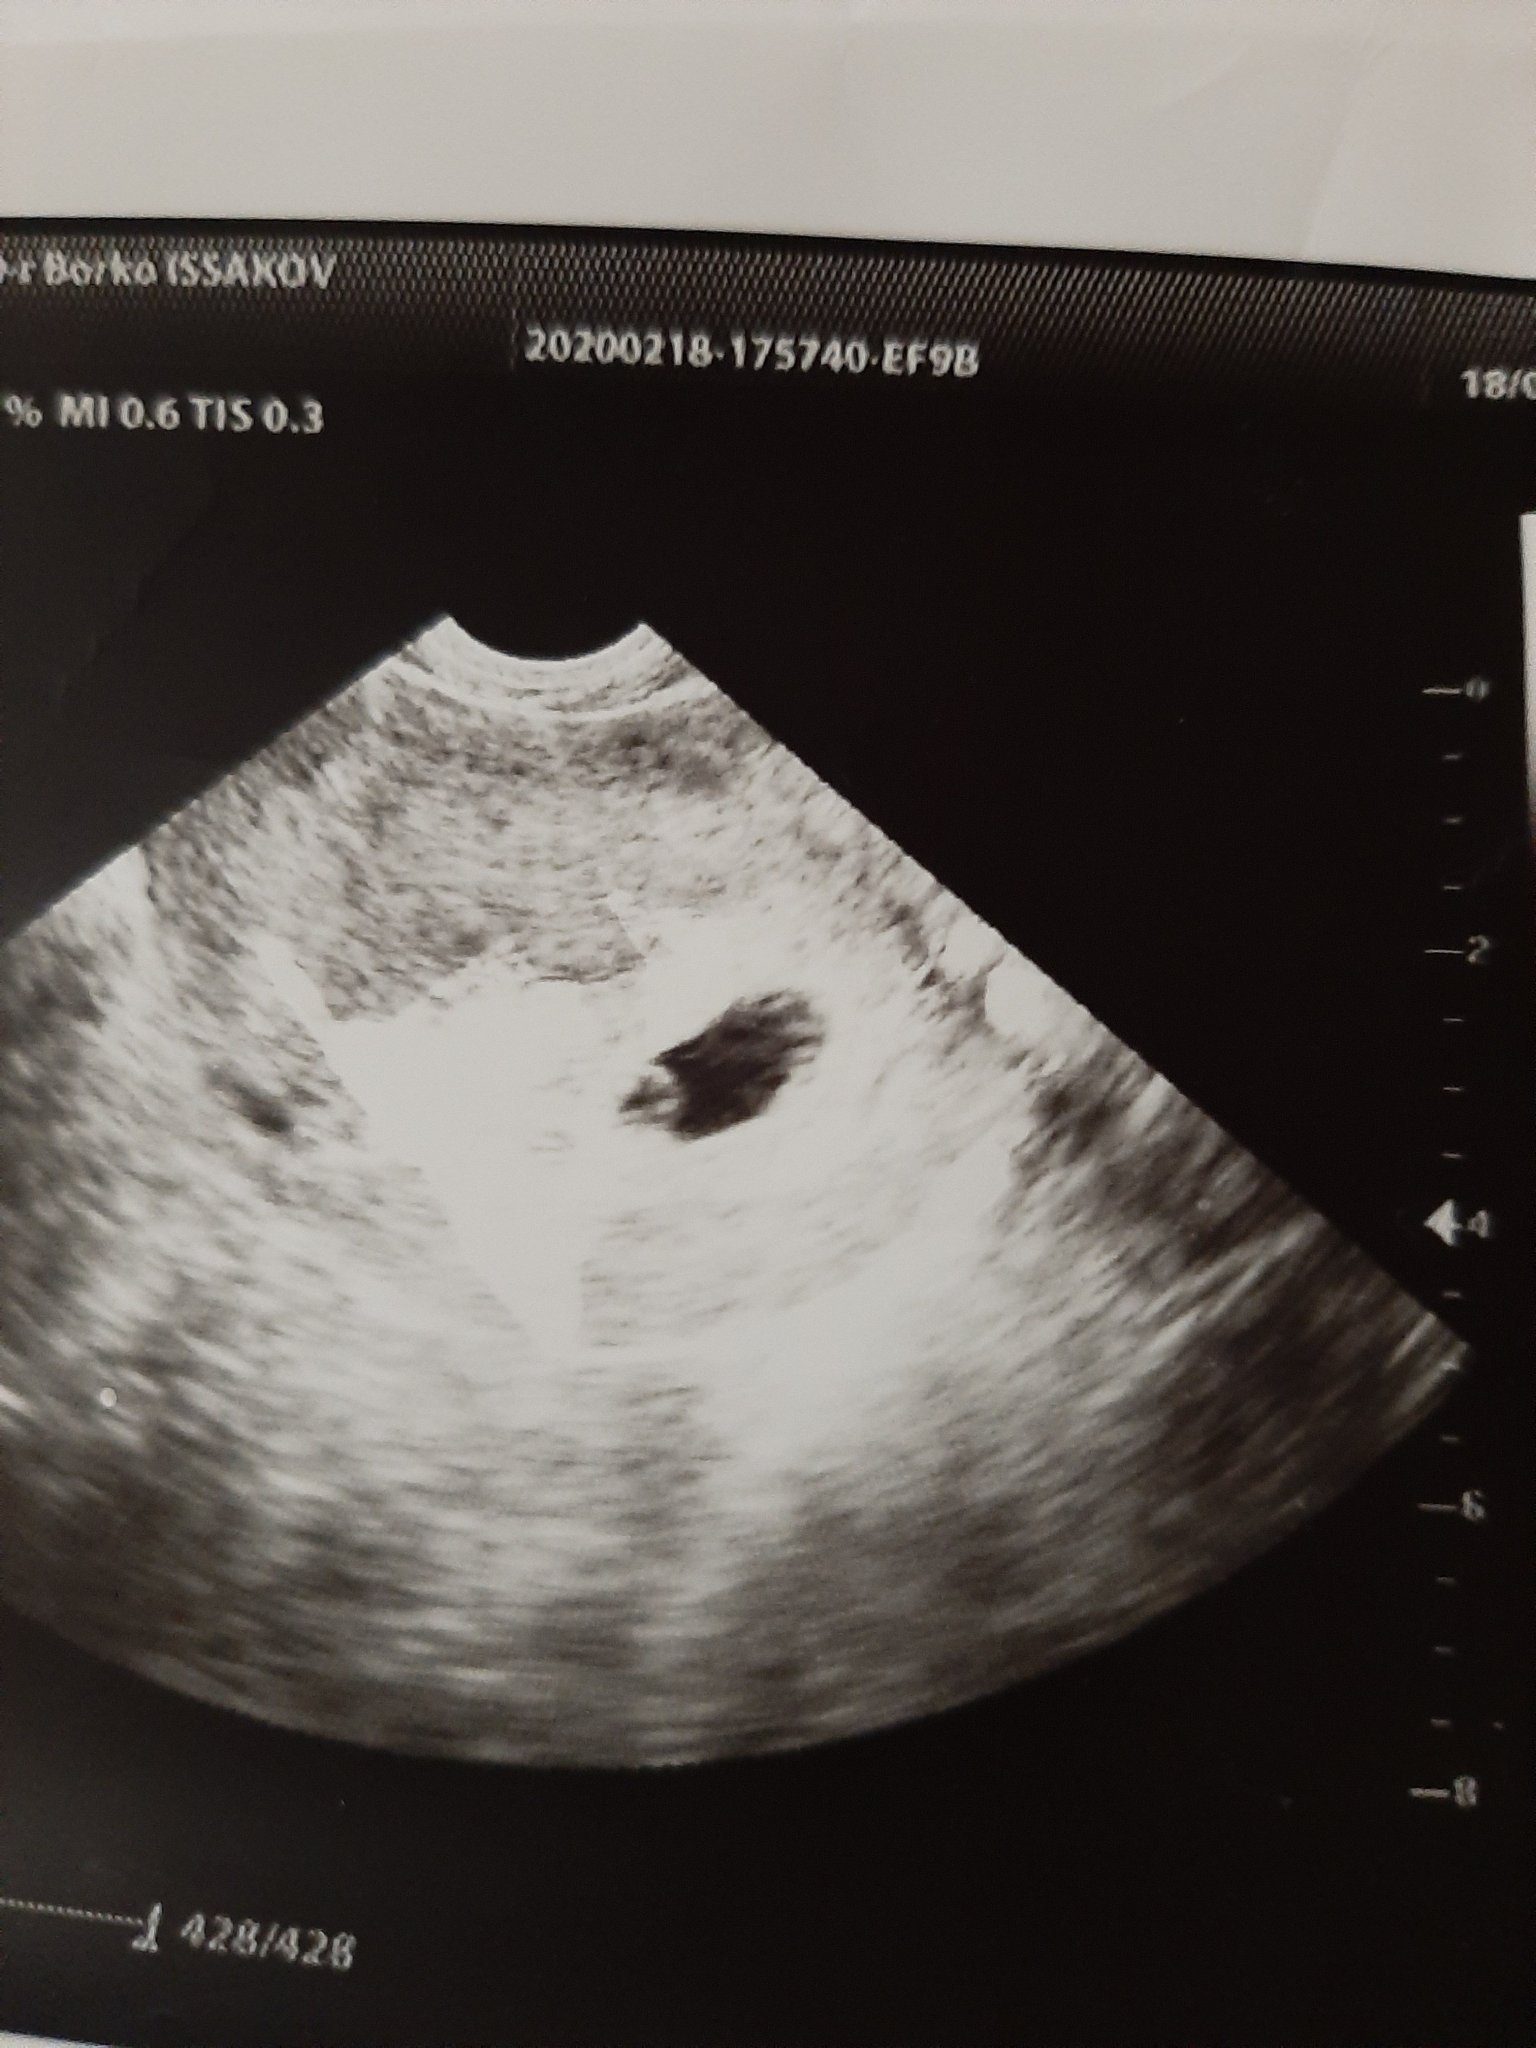

Как мина феталната морфология и какви бяха резултатите от скрининга за хромозомни аномалии?